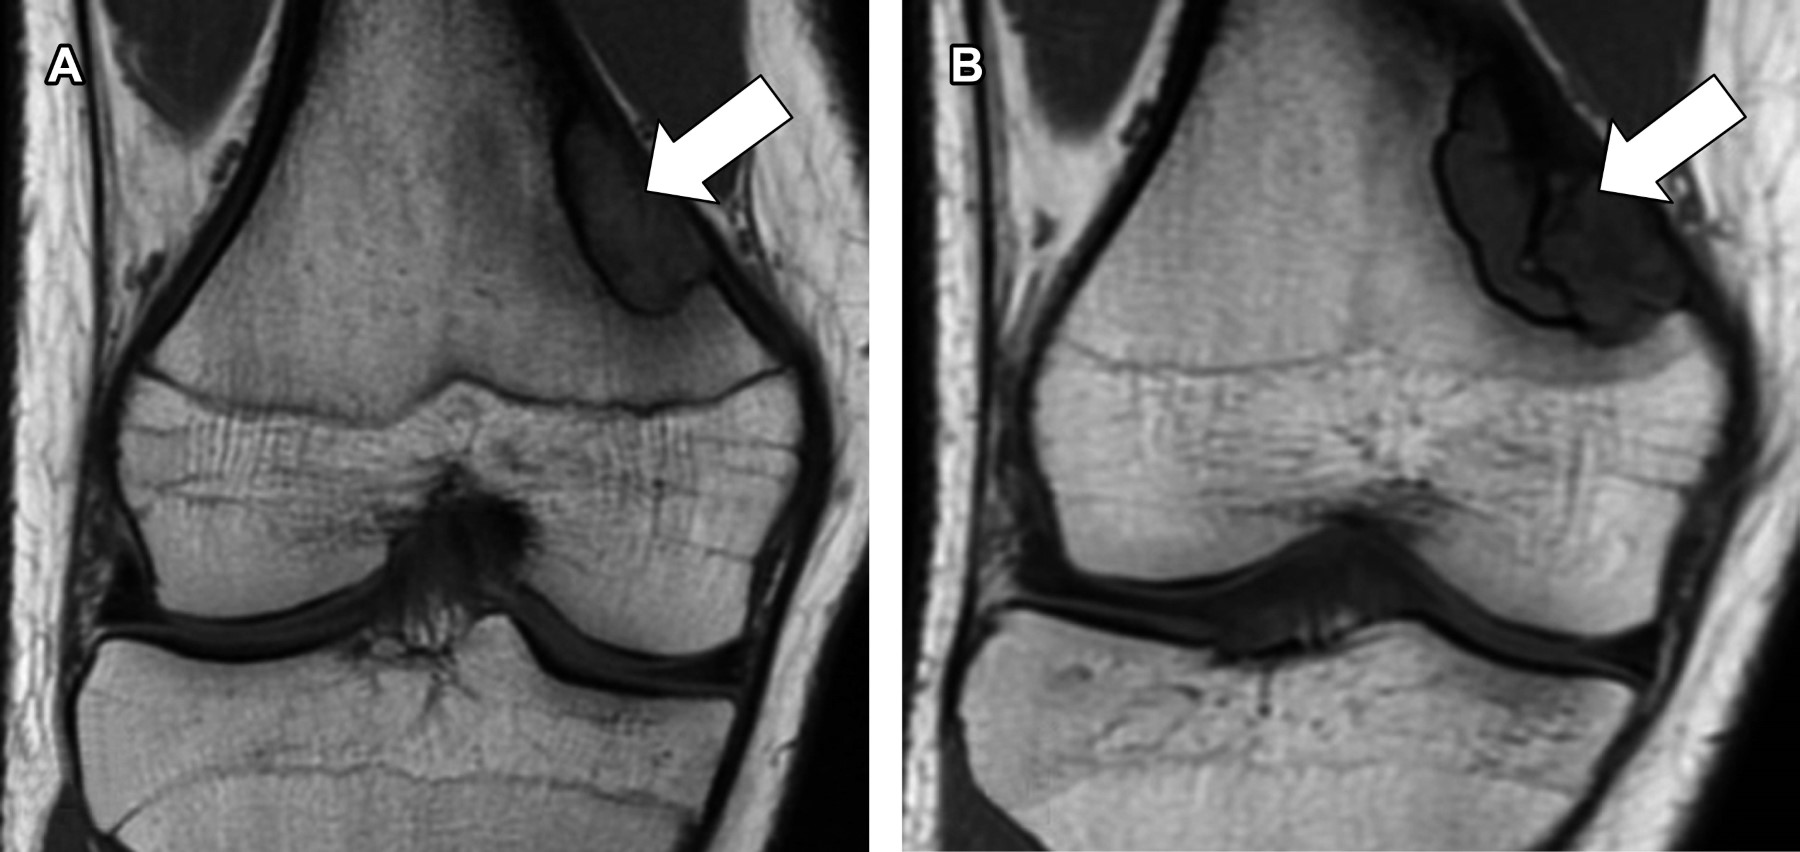

Chronological evolution of bilateral non-ossifying fibroma

Non-ossifying fibroma, a benign bone lesion, is a developmental defect that appears in the metaphyseal region of long bones and advances towards diaphysis secondary to bone growth. These lesions are mainly found in children and predominately in the male gender and are characterized by being asymptomatic; however, their existence predisposes them to pathological fractures. The diagnosis of non-ossifying fibromas is mainly based on their characteristics by imaging methods and is considered "leave alone" lesions due to their benign and self-limiting natural history.

Figure 2